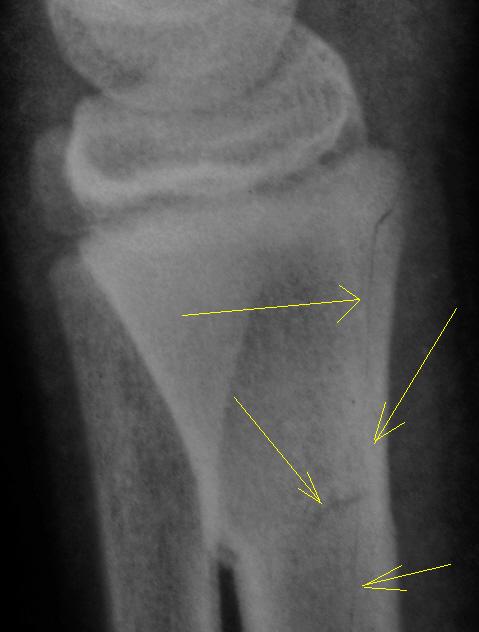

Травма. Пациент направлен хирургом в рентгеновский кабинет для рентгенологического исследования лучезапястного сустава.

Как будем характеризовать линию перелома коллеги?

Вот она - натуральная  "зеленая ветка"!!!

показательный снимок этого перелома

Дело в том, что в данном случае не одна а несколько линий перелома.

Кроме основного – "зеленая ветка" – другой недостоверен: может быть артефактом. На боковой рентгенограмме полоса слишком чёткая для нерезкого в целом снимка, похожа на полосы в области запястных костей. Там нет переломов? Подмигивает В прямой проекции обе линии принадлежат поднадкостничному перелому.